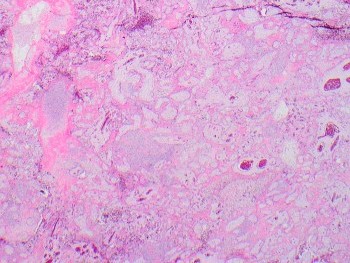

A 64 year-old man with history of clear cell renal cell carcinoma s/p nephrectomy (2021) presents with scrotal pain and firmness. Ultrasound reveals a 2 cm solid lesion. Serum tumor markers (hCG and AFP) were normal. The tumor was negative for SALL4, OCT3/4, AFP, and showed focal patchy positivity for pancytokeratin (focal). PAX8 was weakly positive. Additional stains are displayed in the pictures.